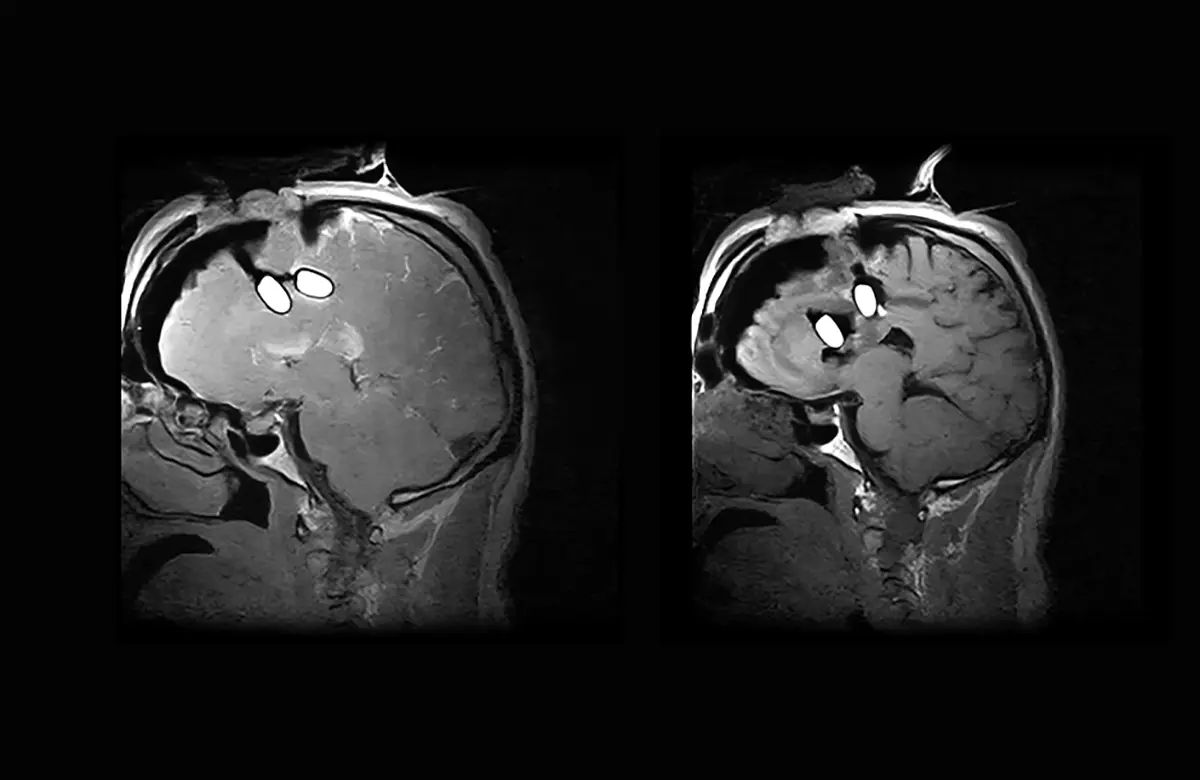

MRI is available during surgery, providing images at the crucial moment in addition to the post-operative follow-up

Advanced intraoperative imaging provides neurosurgeons with the clarity, and confidence required to make important decisions in critical moments.